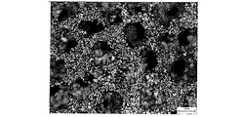

粒径:約45μm〜約75μmの市販の純チタン粉末(Phelly Materials, Inc. Bergenfield, NJ, USA)、および、PFAとしての粒径:約250μm〜約425μmのNaCl(Fisher Scientific International Inc. Hampton, NH, USA)を、Ti:PFAの体積おおよそ25:75の比率で混ぜ合わせた。Ti:PFA混合物100cm3あたり約700μLに相当する量で逆浸透水を加えた。この混合物を型に加え、約22ksi(約151.7MPa)の圧縮圧力で素地になるよう圧縮した。NaClが溶解するまで、素地を水浴中に置いた。結果として得られた金属骨格を約4時間65℃で乾燥して、次に2時間1204℃で焼結した。焼結した金属フォーム構造が図3〜6に与えられており、これらの図は、複雑な形状の多孔性が高い金属フォーム構造を示している。<Example 1>

Particle size: Commercially pure titanium powder (Phelly Materials, Inc. Bergenfield, NJ, USA) of about 45 μm to about 75 μm, and particle size as PFA: NaCl of about 250 μm to about 425 μm (Fisher Scientific International Inc. Hampton, NH, USA) were mixed in a ratio of Ti: PFA volume of approximately 25:75. Reverse osmosis water was added in an amount corresponding to about 700 μL per 100 cm3 of Ti: PFA mixture. This mixture was added to the mold and compressed to a green body with a compression pressure of about 22 ksi (about 151.7 MPa). The substrate was placed in a water bath until the NaCl dissolved. The resulting metal skeleton was dried at 65 ° C. for about 4 hours and then sintered at 1204 ° C. for 2 hours. Sintered metal foam structures are given in FIGS. 3-6, which show complex shaped highly porous metal foam structures.